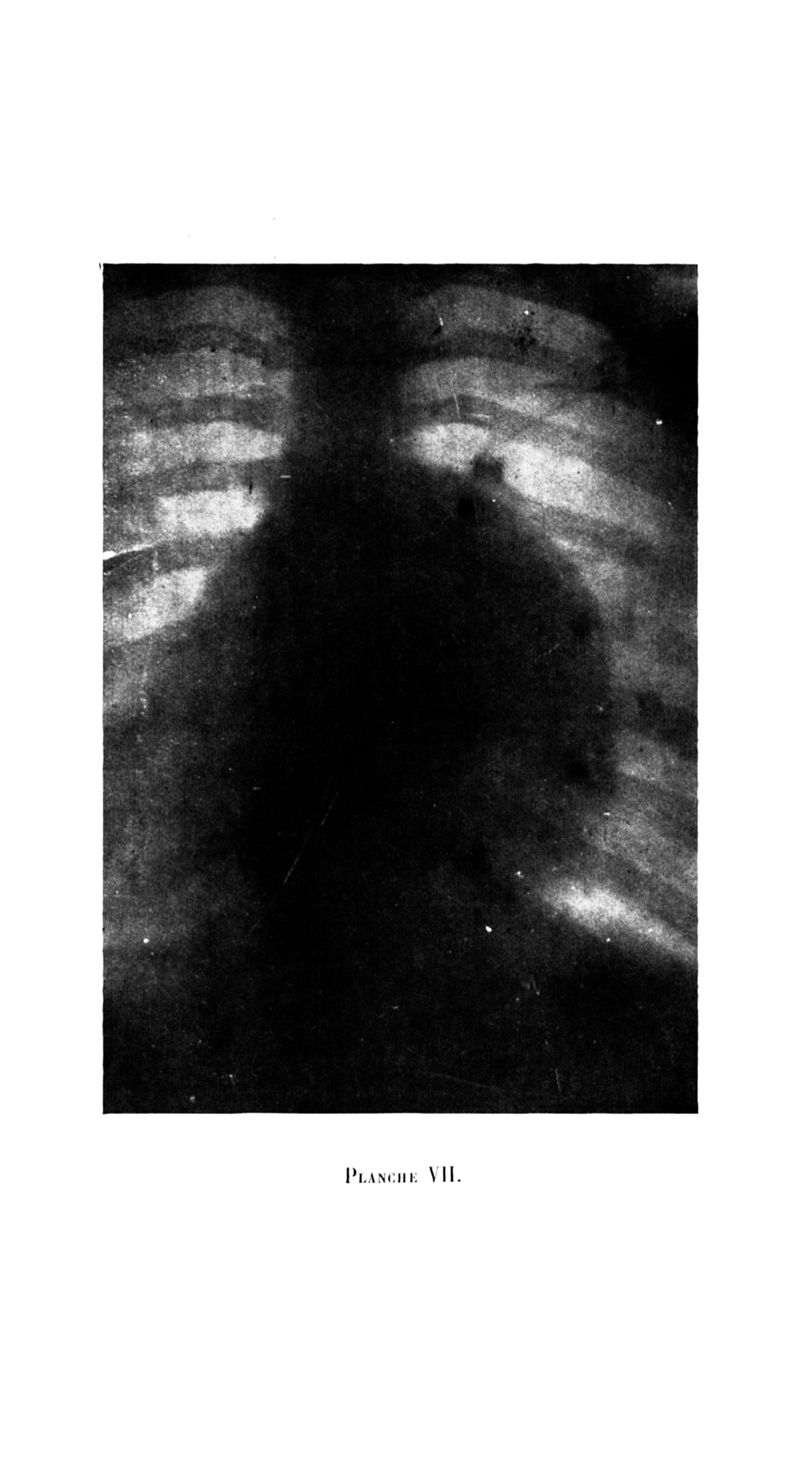

Archives de médecine et pharmacie navales

1924, n° 114. - Paris : Imprimerie nationale, 1924.